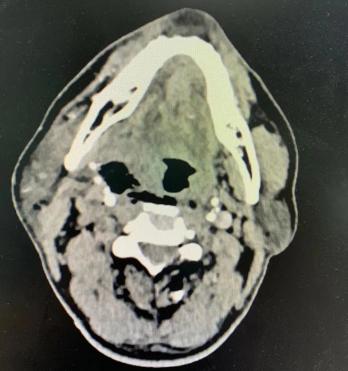

上午十点受伤,到下午送入广西医科大学第一附属医院急诊,时间一分一秒过去。医院立即启动绿色通道,陆先生被送入抢救室,维持生命体征平稳。放射科、检验科等多学科积极配合,完善入院和术前检查,很快陆先生的病情便“水落石出”。

幸运的是树枝扎入的位置虽然紧邻颈血管鞘,紧紧擦着血管壁扎入,但未刺破颈鞘内的大血管,也并未伤到颅脑,患者还合并左侧胫腓骨下端粉碎性骨折。医生最担心的是松解后出现颈总大动脉破裂大出血。医务部迅速组织多学科团队会诊,制定了周密的手术方案。

14厘米的树枝穿通颈部触及颅底后受力已经弯折,紧贴着血管颈内静脉和颈总动脉,而且插入的位置很高很深,尖端上抵颅底,外侧又有下颌骨阻挡,操作空间很有限。连耳鼻咽喉外科特有的电刀和钳子都难以伸进去止血。如果出现颈动脉大出血,后果不堪设想。麻醉科利莉副主任医师首先为患者打开气道,保证呼吸畅通,开通深静脉通道,为可能出现的大出血抢救做好准备。

术中,张哲带领手术团队沿着树枝入口处皮肤做T形切口,充分暴露分离颈内静脉和颈总动脉,并用标识带预结扎。然后小心翼翼地把树枝周围肌肉分离松解,一直到近颅底处树枝末端附近。张哲将嵌顿的树枝充分松解后,迅速将其拔出,并快速止血。经过1个多小时的努力,这颗“埋”在颈部血管旁边的“地雷”终于被成功摘除。随后,王静威接力,为陆先生行左小腿清创缝合石膏固定初步治疗。术后,陆先生恢复良好,将择期接受进一步治疗。